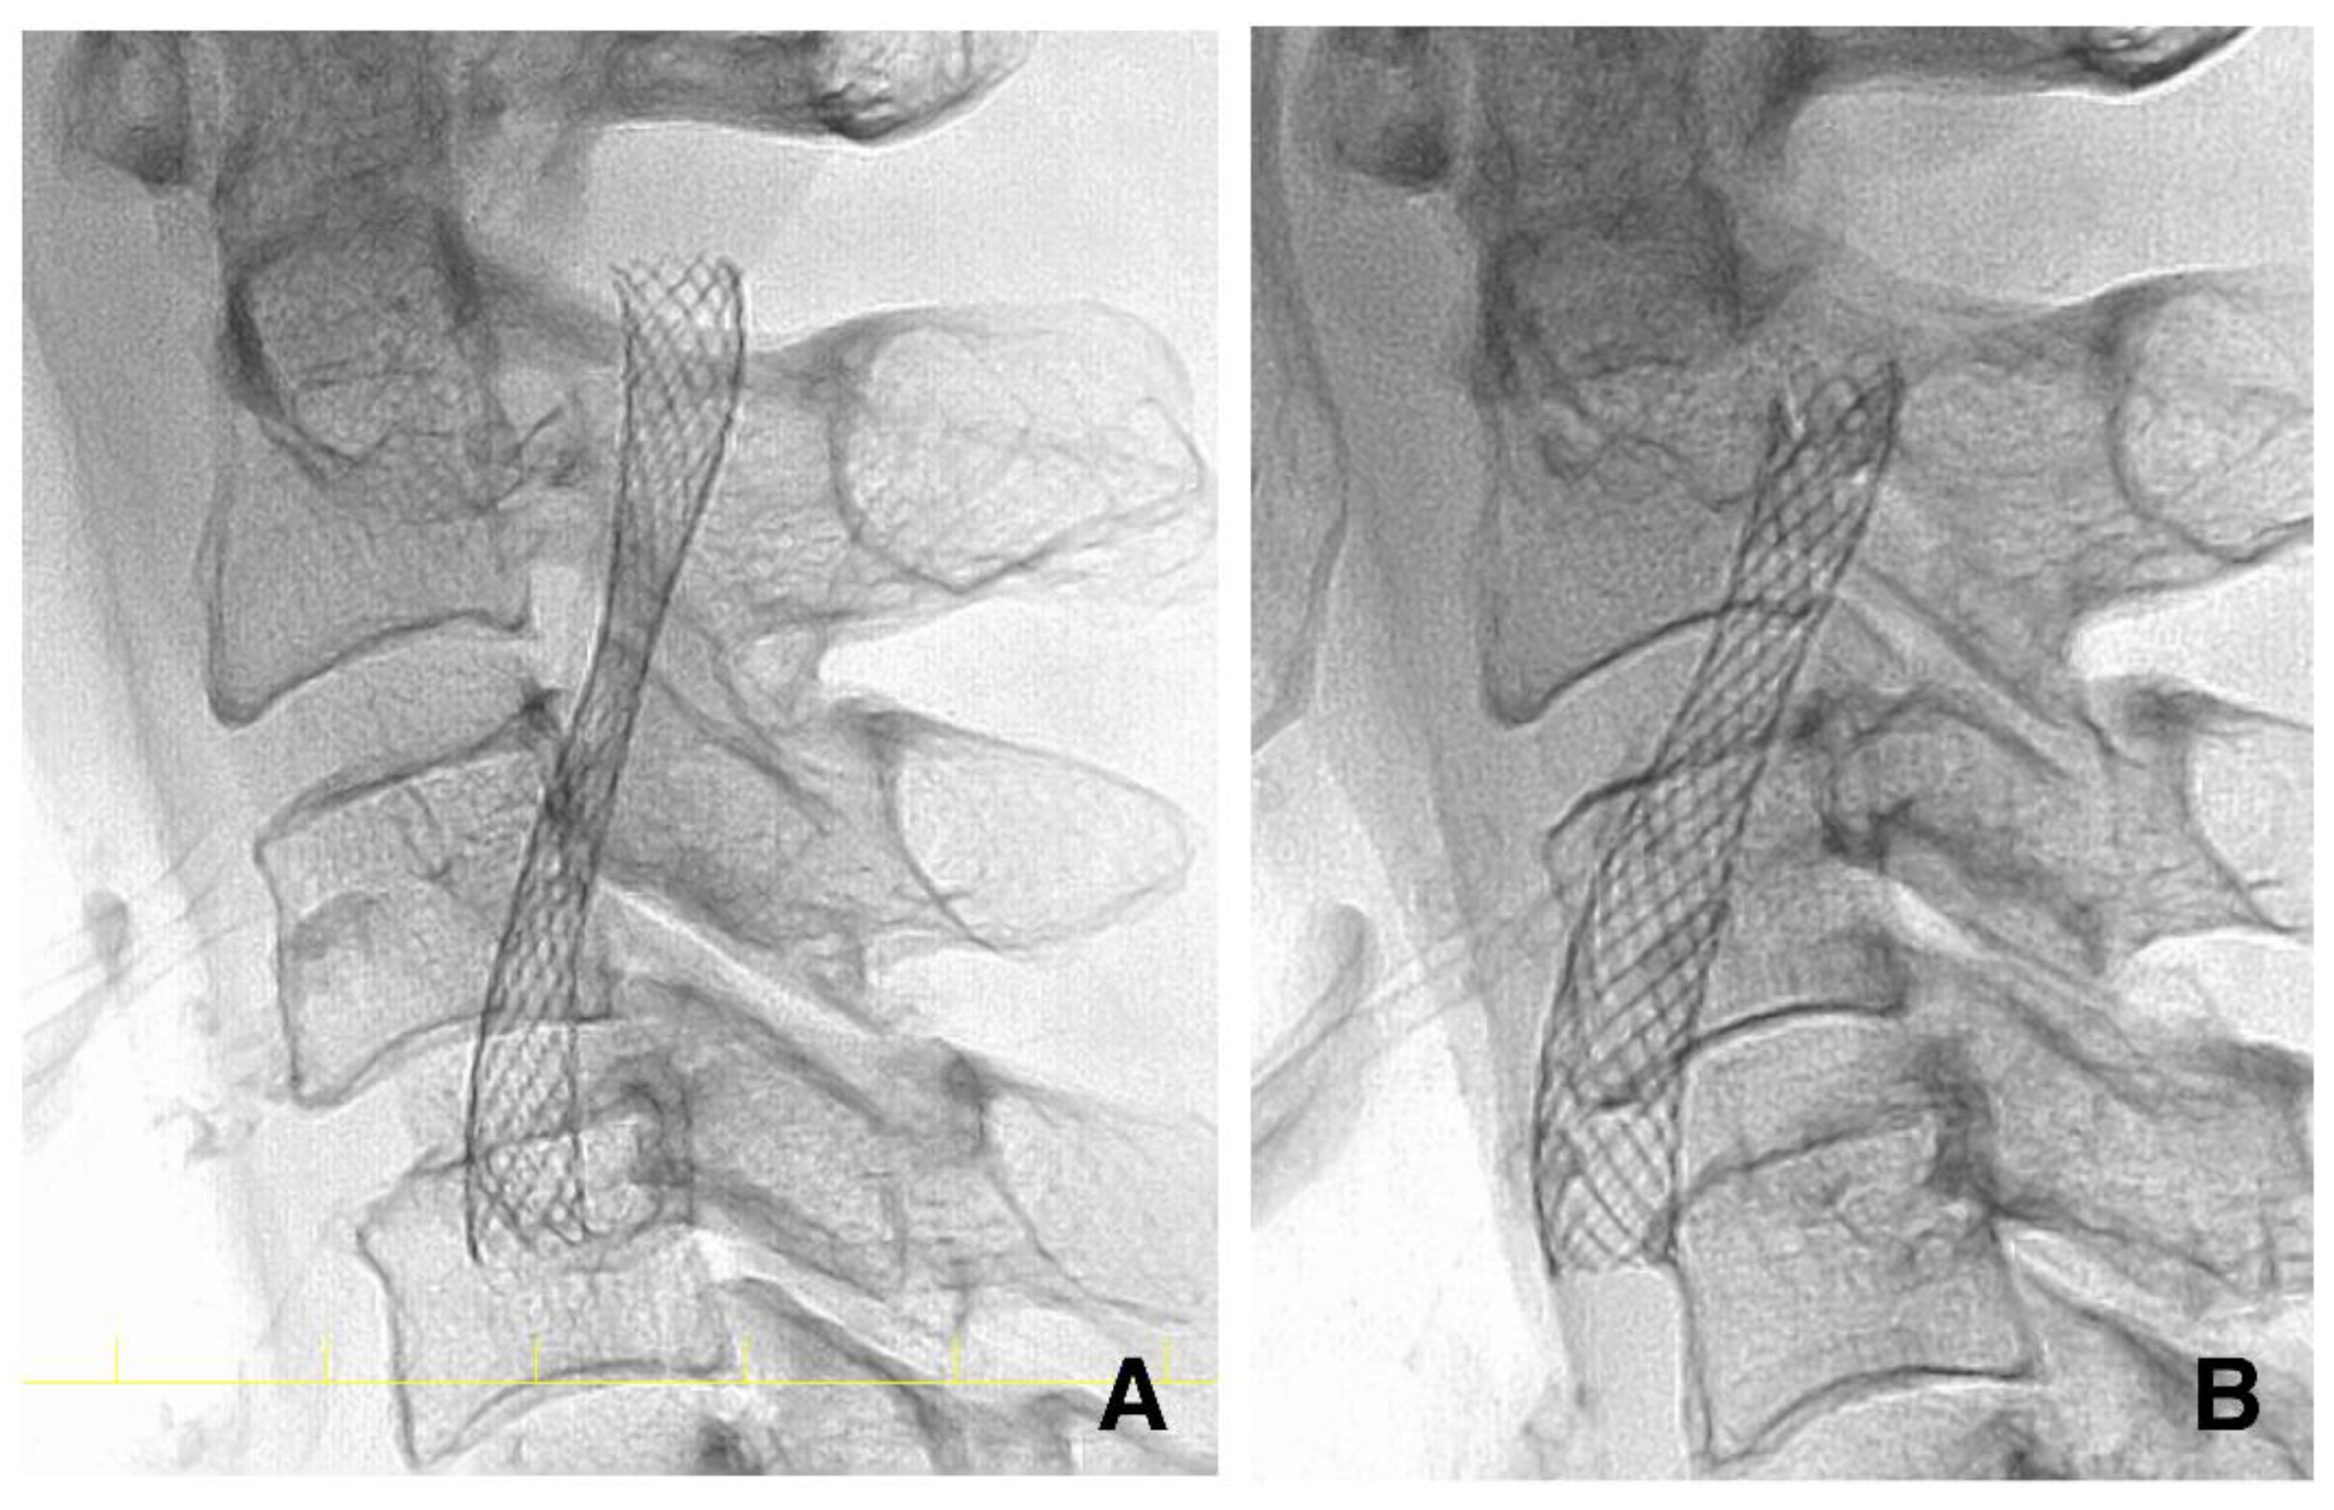

2.7. DSA Investigation after CAS

2.8. Management before and after CAS